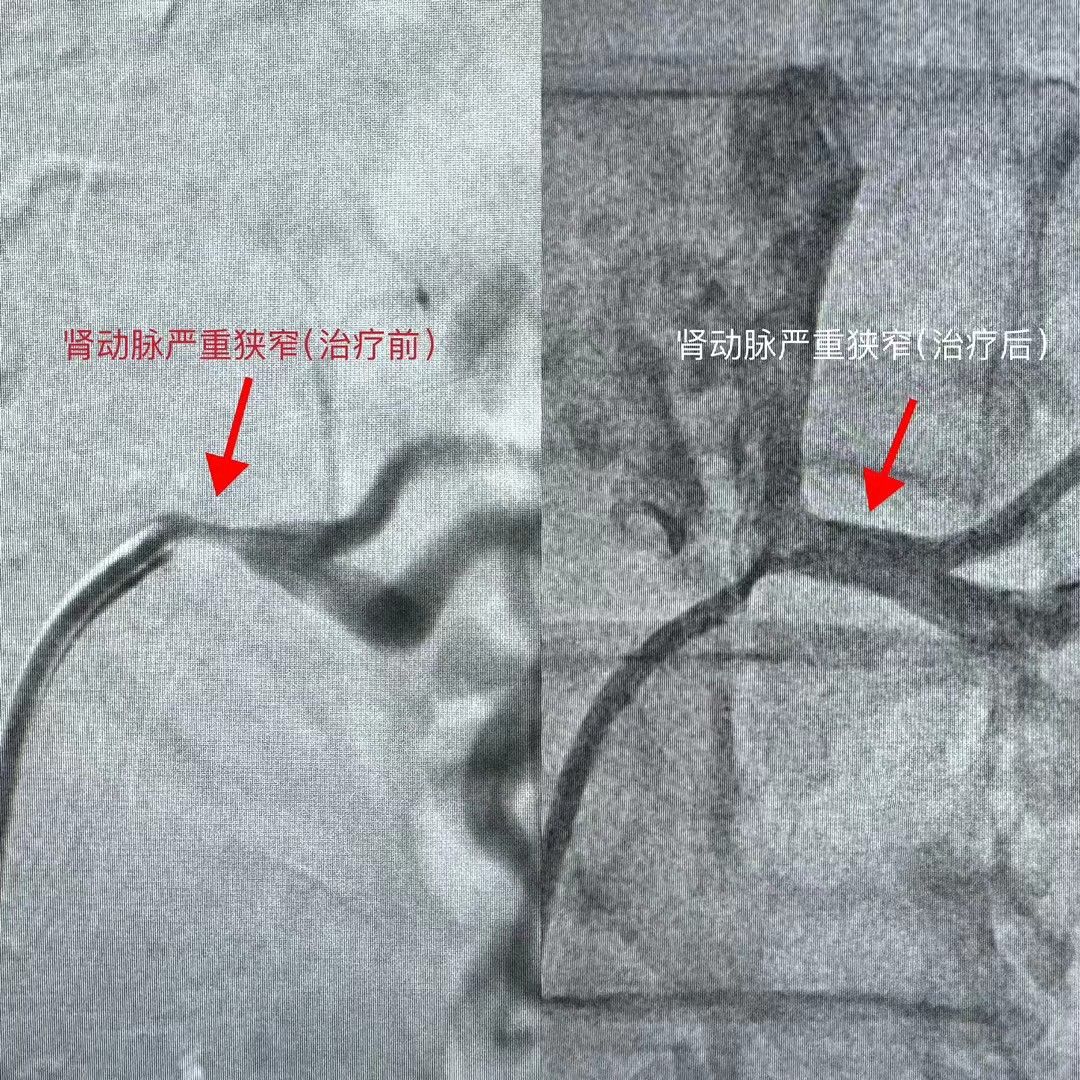

我中心现配有 20 余台医用智能化电子血压计,可实时传输血压数据;20余台 24 小时动态血压监测仪,具备多导心电图,动态心电图,动态血压监测,超声心动图,颈动脉超声多普勒,脉搏波传导速度,无创心功能检测,踝臂血压指数,尿微量蛋白,尿白蛋白定量,眼底检查,计算机断层扫描血管造影,心脏磁共振和动脉造影等检查设备条件和技术。此外,我院于2023年通过港澳药械通项目引入经皮肾动脉交感神经消融术(RDN)的微创手术,成为国内大陆地区首家批准开展RDN的医疗机构。同时开展的肾上腺静脉取血术以及肾动脉狭窄支架植入术等在继发性高血压诊治领域也取得良好效果。

肾动脉狭窄支架术